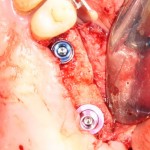

Затем устанавливаются импланты. В данном случае я выбрал импланты Friadent Xive 3.4×13 мм. В принципе, можно было бы использовать имплантаты диаметром 3,0 мм, специально предназначенные для нижних резцов, но, к сожалению, выбор супраструктур для них весьма ограничен:

И второй имплантат:

Импланты закрываем заглушками:

Обратите внимание на то, что мы не погружаем имплантаты слишком глубоко. Полированная фаска имплантата должна находиться выше уровня костной ткани.

Чрезмерное погружение имплантов — одна из наиболее распространенных ошибок в имплантологии, грозным осложнением которой является периимплантит и рецессия десны в области соседних зубов. С этой точки зрения, лучше недокрутить, чем перекрутить.

Затем подготавливаем лунки и устанавливаем импланты Friadent Xive соответствующего диаметра:

Убираем имплантодержатели, а сами импланты закрываем заглушками:

Также обратите внимание, что я не погружаю импланты слишком глубоко — только до края полированной фаски.